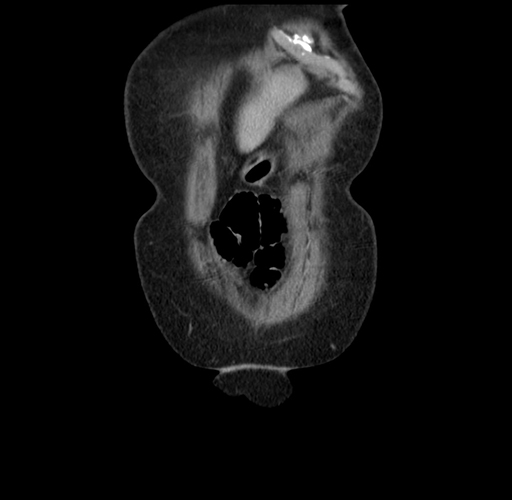

Pre-Chemo: Coronal Venous

Coronal Venous